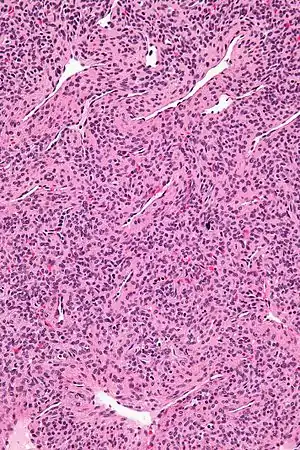

Micrograph of a myopericytoma. H&E stain.

Myopericytoma is a rare perivascular soft tissue tumour. It is usually benign and typically in the distal extremities.[1]